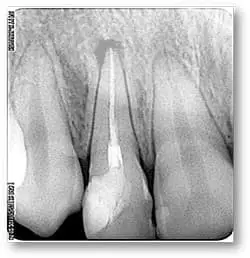

Пациентка Наталья (14 лет) обратилась с жалобами на боли при надкусывании на боковой резец слева (22 зуб). Этот зуб был лечен 2 года назад по поводу осложненного кариеса, под анестезией было проведено удаление нерва, пломбирование канала и постановка композитной пломбы. При осмотре: пломба не соответствует клиническим требованиям, незначительная болезненная реакция на постукивание. Был сделан прицельный снимок 22 зуба.

На снимке изменение костной ткани в области верхушки корня с четкими контурами. Канал запломбирован не плотно, хотя и на всю длину корня.

В день обращения пациентки было начато лечение. Старая пломба удалена, корневой канал распломбирован, обработан ультразвуком, в канале турунда с антисептиком, зуб закрыт временной повязкой. Через 2 дня канал запломбирован лечебной пастой, гранулема также заполнена лечебной пастой. Сделан контрольный снимок. Зуб герметично закрыт временной пломбой.

На снимке видно восстановление костного рисунка (гранулема полностью исчезла вместе с лечебным материалом). В канале лечебный материал сохранен. Теперь можно перейти к завершающему этапу лечения: пломбирование канала постоянным материалом и постановка композитной пломбы. После пломбирования канала обязательно делаем снимок контроля качества пломбирования.

Лечение кисты заняло по времени 3 месяца, но тем самым мы избежали хирургического вмешательства и возможного удаления зуба. На снимке видно, что размер гранулемы уменьшился в 2 раза. Объем лечебного материала в гранулеме также уменьшился. Видно образование костного рисунка. Следующий контрольный снимок был проведен через 1,5 месяца.